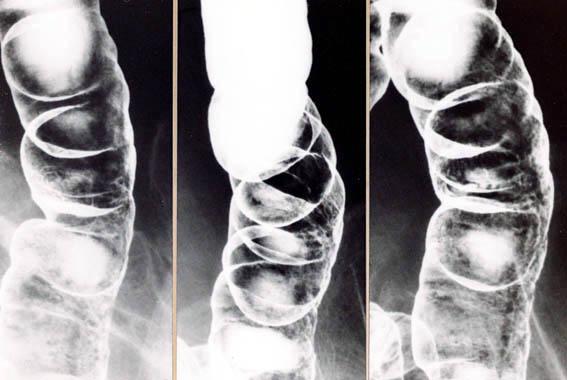

허혈성 대장염

종주궤양의 소견으로부터 허혈성 대장염으로 진단된 예

염증성 및 궤양성질환/허혈성 장염(혈전증 포함)

대장/하행

X-P

40이상